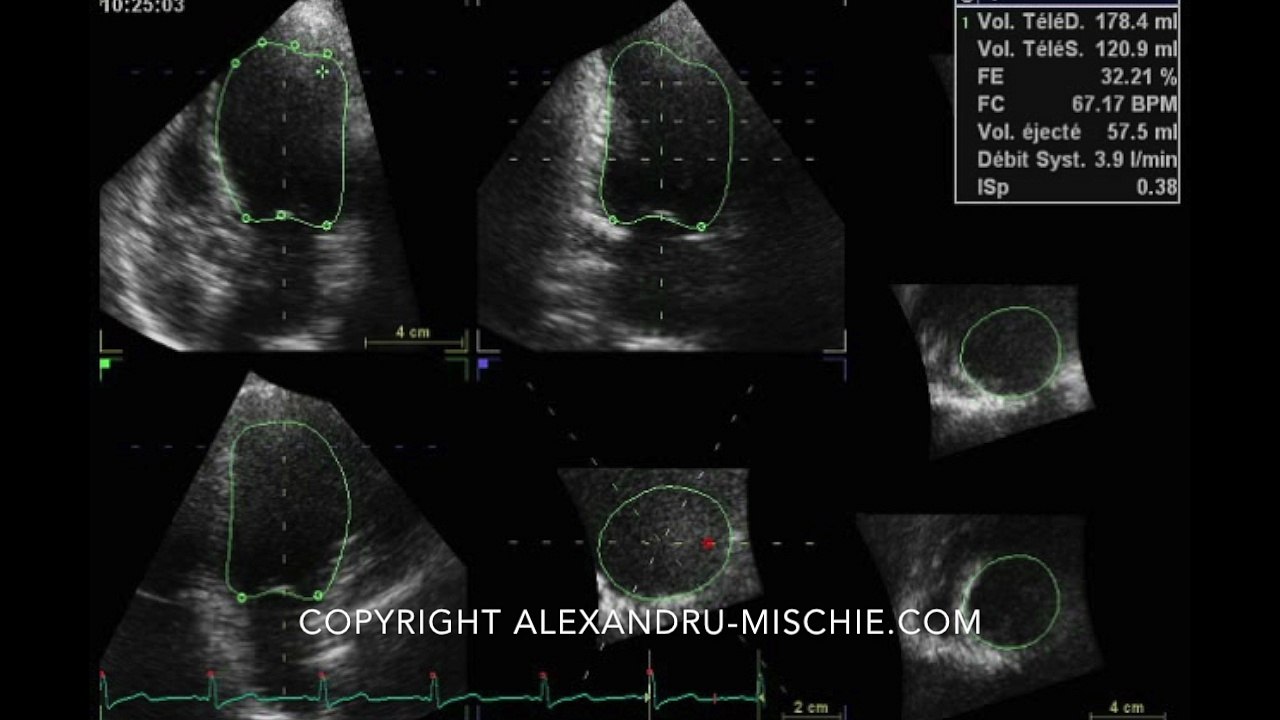

3D LVEF Examples: Left Ventricle Frames

Just a few still frames of 3D ejection fraction of the left ventricle